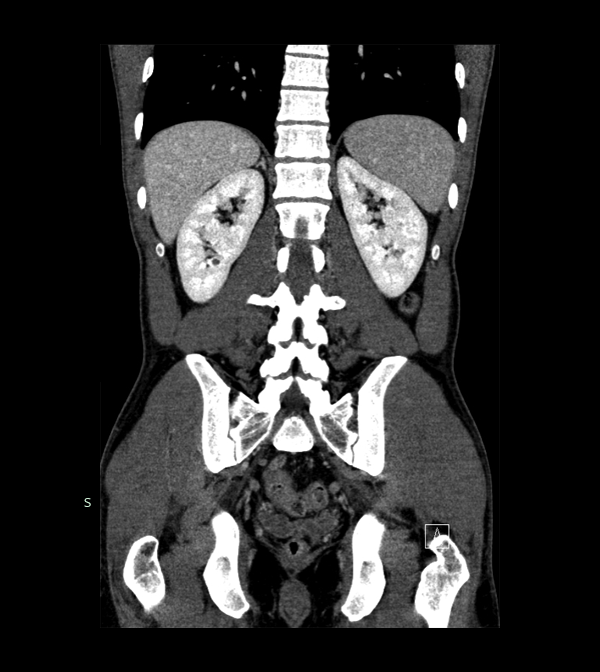

Body

Covers abdominal CT anatomy.